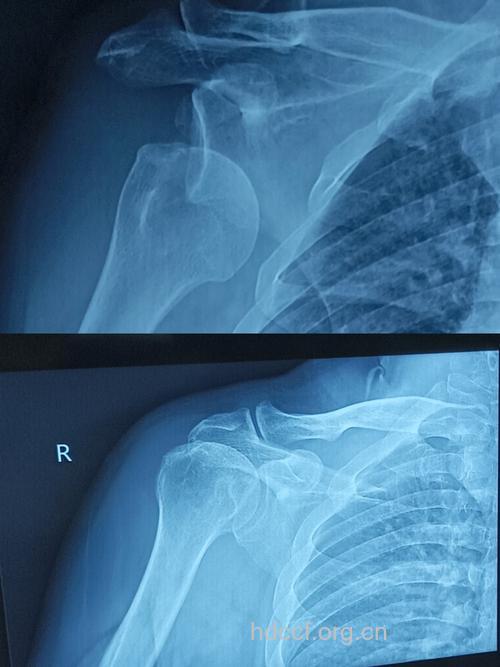

肩关节脱臼的X光片

1.肩关节前脱位:最多见。其中以喙突下脱位尤为常见。正位片可见肱骨头与肩盂和肩胛颈重叠,位于喙突下0.5cm-1.0cm 处。肱骨头呈外旋位,肱骨干轻度外展。肱骨头锁骨下脱位和盂下脱位较少见。 2.肩关节后脱位:少见。值得注意的是正位片肱骨头与肩盂的对位关系尚好,关节间隙存在,极易漏诊。只有在侧位片或腋位片才能显示肱骨头向后脱出,位于肩盂后方。 3.肩关节半脱位:关节间隙上宽下窄。肱骨头下移,尚有一半的肱骨头对向肩盂。